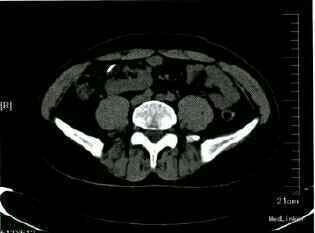

查体:腹平,未见胃肠型,腹软,全腹无压痛及反跳痛,右下腹可扪及一大小7cm×6cm的包块,质硬,无压痛,活动度可,表面皮肤未见异常,双肾区无叩击痛。门诊查血常规:正常。尿常规:隐血2+,白细胞+。泌尿系B超示:左侧异位肾,左肾结石,左肾积水。人院后行CTU+CTA示:左侧异位肾(位于右碰盆腔)及左肾结石,结石长径约1cm。

异位肾为肾脏先天性异常发育,盆腔异位肾常有形态上的改变,大部分较正常肾脏小。表面可呈分叶状,常伴有转位不全,肾盂向前,输尿管可异常缩短,。肾动脉发源在主动脉分叉上方或由其它分支发出,且常伴有其他复合畸形,部分可呈囊性变。较正常肾脏而言,异位肾更易罹患尿路结石及肾盂积水,病因主要是因为肾脏位置异常或旋转不良引起输尿管高位开口或迷走血管压迫上段输尿管或肾大盏引起梗阻。主要表现为腹痛、腰痛、血尿等,由于肾脏位置不同、疼痛性质难以判断,可能被误诊为阑尾炎、胆囊炎,女性还可能被误诊为盆腔附件炎。B超是首选的检查方法,具有经济、简单、安全、可重复、不受肾功能损害影响等优点,但容易造成误诊。CT能更好显示异位肾的位置及其与其他器官的结构关系,明确关系做最好。